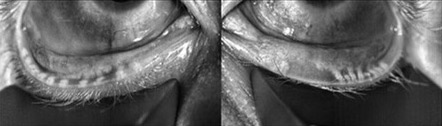

Source: Cynthia Matossian, MD

When warranted, point-of-care testing should be done, Dr. Matossian continued, noting that this could include meibography, MMP-9 testing, ocular surface and tear osmolarity testing, and a slit lamp exam with vital dyes. She also said to look, lift, push, pull (LLPP), per the ASCRS Cornea Clinical Committee’s Preoperative OSD Algorithm. “Looking at the quality and expressibility of the meibum helps identify these patients,” Dr. Matossian said.